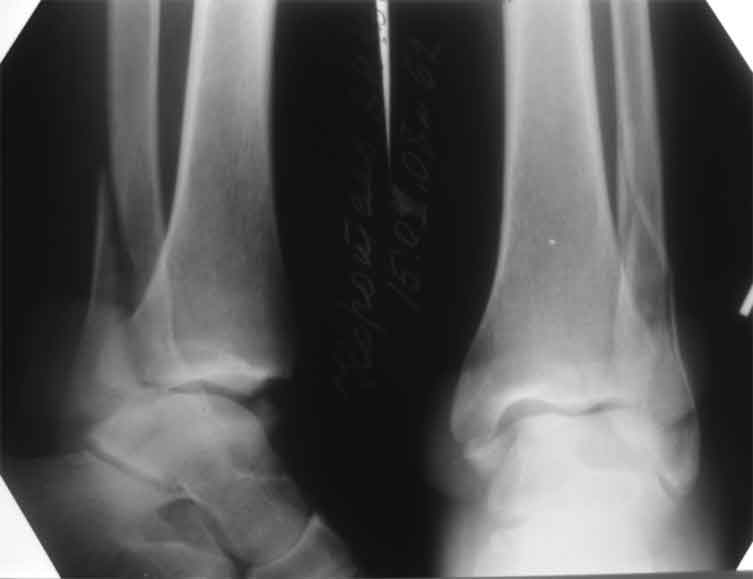

Мне кажется есть все основания попытаться сделать остеосинтез. Боль вследствие нестабильности. Нестабильность вследствие неанатомичного положения дистального отломка малоберцовой кости. Через 1,5 вполне возможно разобщить, репонировать и фиксировать длинный косой перелом наружной лодыжки. Вероятно, одновременно придется делать медиальный доступ для мобилизации внутренней лодыжки. Мы оперируем таких пациентов, функциональные (объем движений) результаты конечно хуже по сравнению с теми кого оперируем в первые 5-10 дней, но вполне удовлетворительные.

Согласен, на предоставленных рентгенограммах все основания для проведения открытого остеосинтеза.

сроки действительно небольшие, но если мы его и возьмем, то пройдет еще минимум неделя, кроме того смущает впечатление сращения н/лодыжки, похоже, что придется не разобщать,а остеотомировать, формирование оссификатов в полости сустава с медиальной стороны, да и сам пациент 1,5 месяца по поводу своей травмы сильно не напрягался